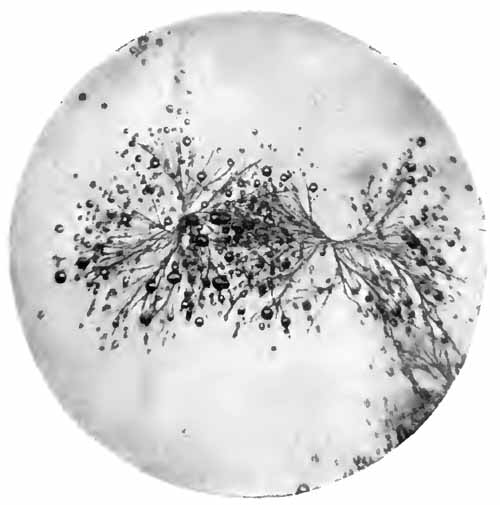

Fibrinous bronchial cast

FIG. 7.—Fibrinous bronchial cast (Sahli).

4. Fibrinous Casts.—These are fibrinous molds of the smaller bronchi. Their size varies with that of the bronchi in which they are formed. They may, rarely, [p. 31] be three or more inches in length. When large, they can be recognized with the naked eye by floating them out in water; when small, a low power of the microscope must be used. They are easily recognized from their branching, tree-like structure (Fig. 7).

Fibrinous casts are characteristic of fibrinous bronchitis, but may also be found in diphtheria of the smaller bronchi. Very small casts are often seen in croupous pneumonia.